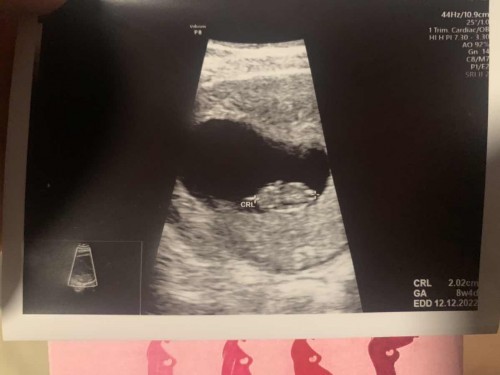

8W เจอเจ้าจิ๋วดุ๊กดิ๊กและเสียงหัวใจครั้งแรก

ตื่นเต้นมากเลยค่ะได้ยินเสียงหัวใจครั้งแรก มีแม่แม่ทีมธันวาคมไหมคะ มาแชร์กันค่ะ ♥️#แนะนำการบำรุงอาหารได้เลยนะคะ #ขอบคุณค่ะ